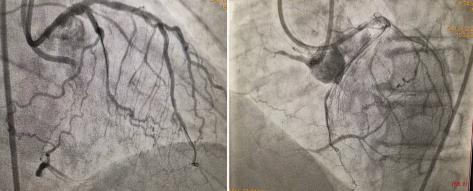

2021年9月26日秋雨绵绵,患者双侧指引导管造影示:如图1。

图1:右冠近段闭塞,前降支-穿膈支-后降支侧枝循环形成CCI级,J-CTO评分4分-高难度CTO病变。